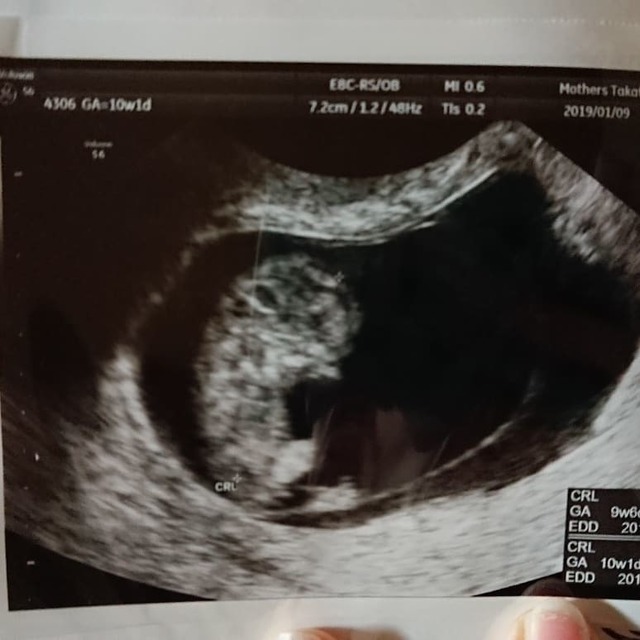

10週1日(10w1d・性別不明)|バドワ さん(29歳)

エコー写真撮影時のエピソード:

産婦人科の先生がまるで自分の孫を見ているかのように、 おいでおいでしてるよ、可愛い可愛い!可愛いね~ と優しく言ってくれてなんだかほっこりしました。

鉄分を積極的に摂りすぎてちょっと多く摂りすぎていると助産師さんに教えてもらいました(笑)

旦那はいつも受診に一緒に来てくれているのでいつも二人でエコー写真に無言で見とれてしまいます(笑)